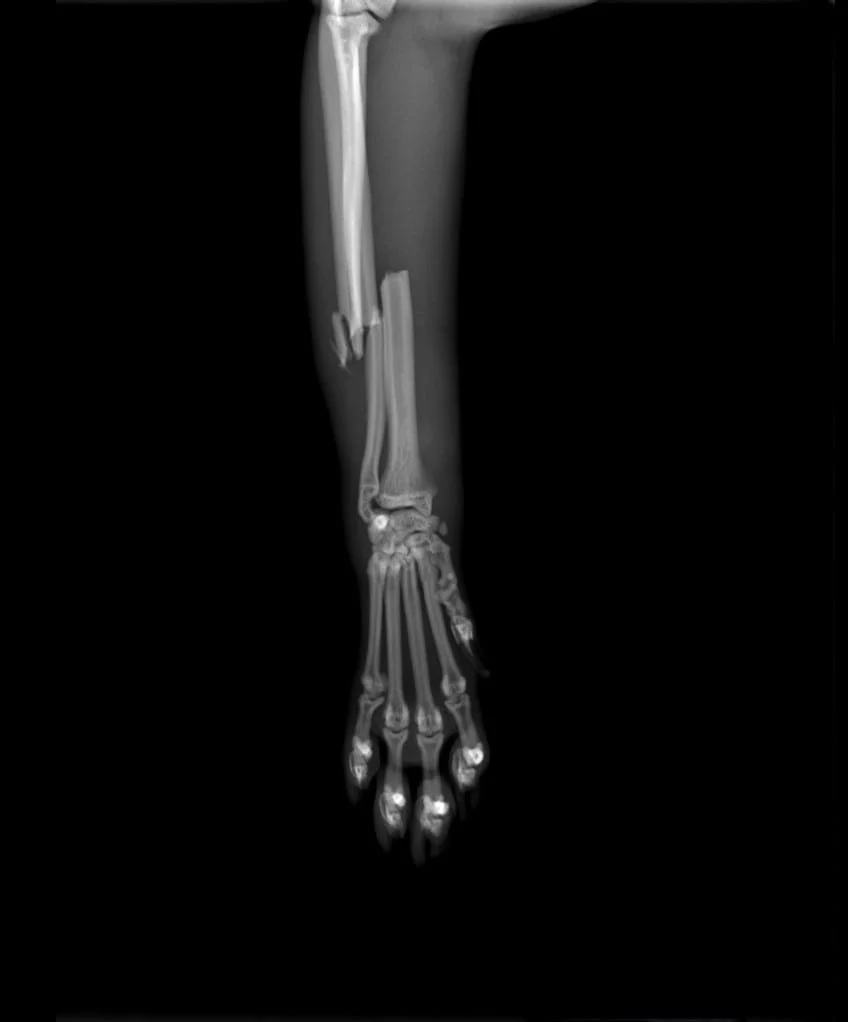

Traumatic Radio-ulnar fracture in a cat

Female, 4 years old, 5 kg domestic short hair indoor cat

presented with acute onset of 5 grade right hindlimb lameness

Radiographic exam reveal complete closed trasverse

mid-diaphyseal radius fracture and short oblique

mid-disphyseal ulnar fracture with small lateral butterfly fragment, with caudo-medial displacement.